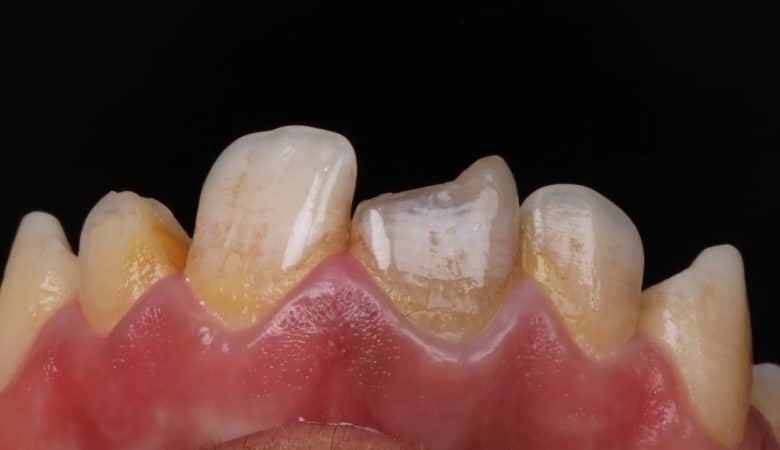

The case presented below is for a 28 year-old female patient. She had multiple spacing in her maxillary anterior segment. The treatment options for such case would be orthodontic treatment (i.e., which is the ideal treatment option), indirect restorative approach,…